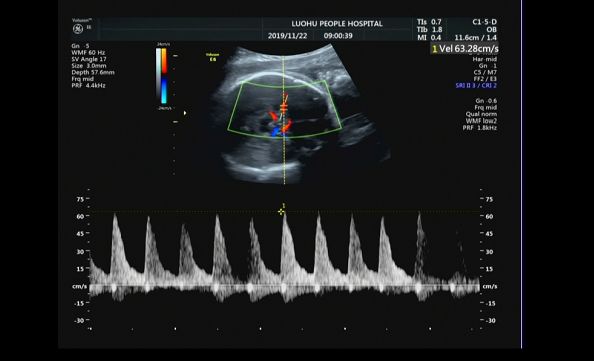

在超声的引导下,一根细长的穿刺针准确的刺入胎儿的脐静脉,经母胎医学团队精确计算的35ml浓缩红细胞缓慢匀速地输入到宝宝体内,宝宝的心跳开始变得有力起来,血红蛋白浓度上升到73g/L。2天后,第二次胎儿宫内输血顺利完成,再次输入55ml血液后,宝宝的大脑中动脉峰值血流速度下降至63cm/s,胎儿血红蛋白浓度上升124g/L。宝宝安全了!

输血前胎儿MCA PSV 63 cm/s